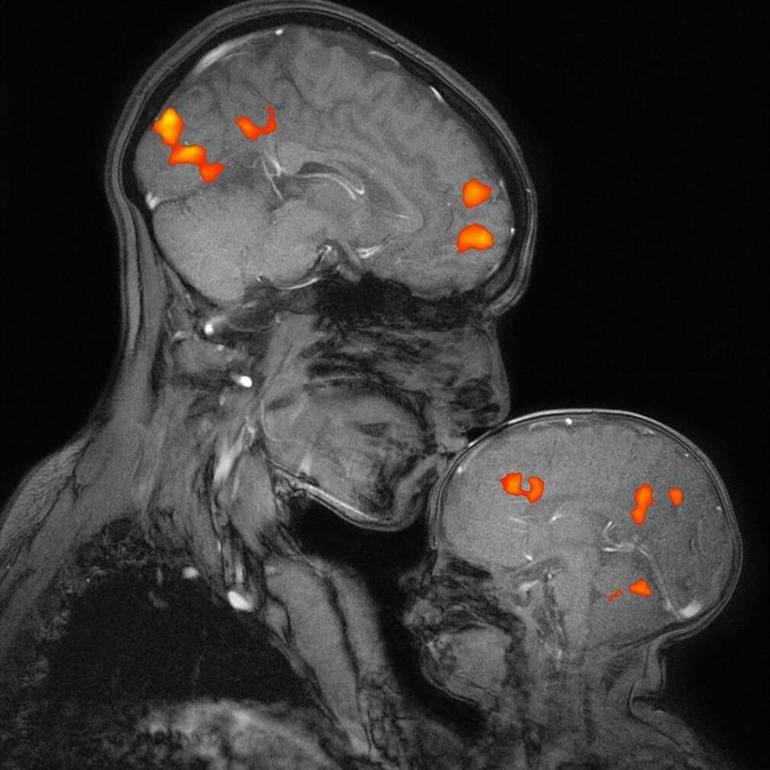

Исследования, лежащие в основе репродуктивной биологии, говорят о том, что ощущение младенцем тела матери помогает ему регулировать свою физиологию лучше, за счет физиологического состояния тела матери рядом (Hofer 2005). Материнский контакт обеспечивает необходимое физиологическое становление и создание эпигенетических условий, когда происходит развитие нервных связей среднего мозга ребенка (Meaney & Szyf 2005). Младенцы плачут из-за отсутствия материнских "сенсорных регуляторов": они испытывают дисрегуляцию (Christensson et al., 1995; Hofer, 2005). Это отключает гормон роста ребенка и включает выделение кортизола (Hofer, 2005). Кортизол "забирает" все калории и другие "неврологические ресурсы" для обеспечения выживания, так что гомеостаз восстанавливается, но за счет снижения развития младенца. Да, в итоге младенец "успокаивается", но энергия, потребляемая для достижения этого гомеостаза не измеряется (McEwen & Seeman, 1999). Когда мать обеспечивает регулирование физиологических процессов ребенка через свое тело, вся энергия ребенка доступна для его развития. Ребенок более спокоен и не испытывает стресса от неспособности справиться с окружающей "одинокой реальностью".

Нам известно, что с более высокой активностью автономной нервной системы требуется больше калорий; это сопровождается высокими уровнями кортизола. Когда кортизол выполняет регуляцию, в физиологии ребенка программируются менее эффективные гомеостатические "установки". Эти "установки" остаются на всю жизнь (Hochberg et al., 2011). Наиболее хорошо известный эффект этого "перепрограммирования" - ожирение (Stettler et al., 2005), также по некоторым исследования гипертония, высокий уровень холестерина и диабет могут стать вероятными последствиями из-за таких изменений (Coe & Lubach 2008). Кроме того, ослабление у младенца связи между миндалиной и лобной доли (Schore 2001b) и способность ребенка доверять будут также в некоторой степени нарушены, когда основные "потребности" ребенка не были выполнены (Ross & Young 2009).